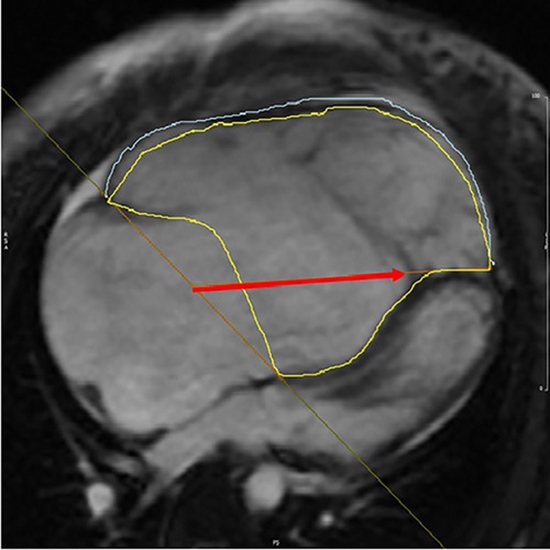

Background: Ebstein's anomaly (EA) is a congenital heart disorder characterized by abnormal function of the tricuspid valve. There are several ways to study tissue composition using magnetic resonance imaging (MRI). One of the most accurate methods is strain calculation using the feature tracking (FT) technique. Due to the novelty of the FT technique in cardiac magnetic resonance (CMR) imaging, there is a lack of comprehensive guidelines to conduct FT-MRI and to present a quantitative report. The current study is aimed to evaluate the FT technique in EA patients and to compare the obtained numerical values with those of healthy individuals.

Methods: A total of 33 individuals were enrolled in a study conducted in 2018-2019 at Shahid Rajaei Hospital, Tehran, Iran. Radial, longitudinal, and circumferential strain patterns of the left and right ventricles were determined in both the patients and the controls using the FT technique. Data were analyzed using SPSS software, version 22.0.

Results: The results showed a significantly lower left ventricular (LV) radial strain in EA patients compared to the control group (P=0.002). In addition, the right ventricular (RV) global longitudinal strain (GLS) in EA patients was significantly lower than in the controls (P=0.001). Other parameters (LV global longitudinal strain, RV radial strain, LV circumferential strain, and RV circumferential strain) did not differ significantly between the two groups.